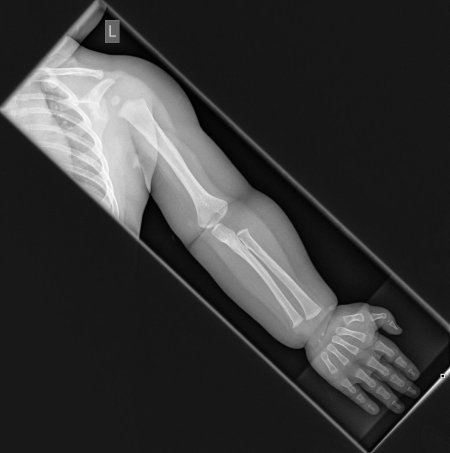

Рентгеновский эффект создает фантастические композиции в этих фотографиях девушки, чье тело становится прозрачным, демонстрируя скелет и внутренние органы. Она позирует в разных позах, ее силуэт светится загадочным свечением. Каждый кадр передает атмосферу научной фантастики и медицинского искусства. Ее кожа кажется полупрозрачной, позволяя увидеть кости и мышцы. Фотографии рассказывают о хрупкости человеческого тела и его внутренней красоте. Девушка то стоит в задумчивости, то делает грациозное движение. Эти иллюстрации вдохновляют на размышления о человеческой анатомии и уязвимости. Каждая картинка - это момент прозрения, когда внешнее уступает место внутреннему. Девушка воплощает образ современной Медузы, сочетающей красоту и загадочность.

Сквозь материю: тайны анатомии